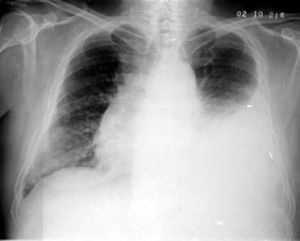

本徵系指由於盆腔腫瘤伴發腹水和胸腔積液並且腫瘤切除後腹水及胸腔積液仍不一定消失的一種綜合徵。

假麥格綜合徵假性麥格綜合徵系非卵巢纖維瘤而為卵巢其他類型的良、惡性腫瘤、胰腺疾患或其他部位腫瘤。假性麥格綜合徵產生腹水多是伴發卵巢輸卵管、子宮或圓韌帶等處的惡性腫瘤尤其是發生腹膜種植或轉移者上皮性乳頭狀癌因乳頭穿破囊壁在腹膜種植,這些種植或轉移至腹膜的瘤細胞可有分泌以及它的分解產物使腹膜受到化學性刺激產生腹水;也可來自卵巢腫瘤破裂,瘤內容物不斷滲入腹腔形成腹水;也可經橫膈或經淋巴到達胸腔,引起胸腔積液。

假性麥格綜合徵的臨床表現與真性麥格綜合徵相似。發生的腹水大多為棕紅色血性腹水,有時混有黏液或瘤內容物腹水黏稠混濁,通過離心沉澱作塗片檢查有時可找到癌細胞,因此做腹腔穿刺採取腹水標本進行檢查,有利於診斷和鑑別。

胸腔積液和腹水於手術後消退又於短期內復發。